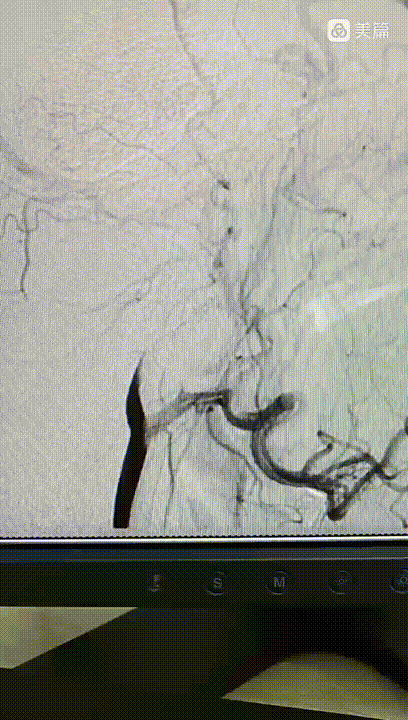

泥鳅导丝、130cm西蒙导管、Neuron MAX长鞘同轴到达C1段到达S迂曲。

Neuron长鞘高到位有助于起到近端阻断作用。

引入6F通桥中间导管。打开中间导管尾部裸奔通过S型迂曲到C5段导管。

尾部流血停止,说明到达狭窄或血栓部位,连接50mL注射器踹马桶抽吸,抽出30mL血液,见0.5Cm大小硬质血栓。